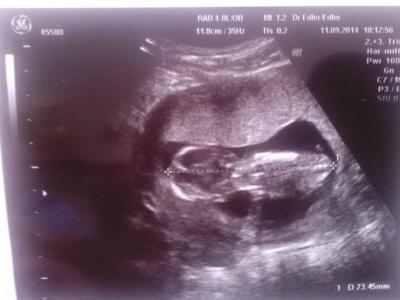

hi mädels also ich komme gerade vom fa und dem baby geht es gut gewachsen ist es auch ich hab meinen arzt gefragt ob es eher nach einem jungen oder mädchen aussieht er sagt danach guckt er nicht erst ab der 20igsten woche ,er meint wenn man vorher guckt ist das wie eine kaffeetasse auslesen

wer von euch weiss denn auch noch nicht? hab heute ein neues bild bekommen :D